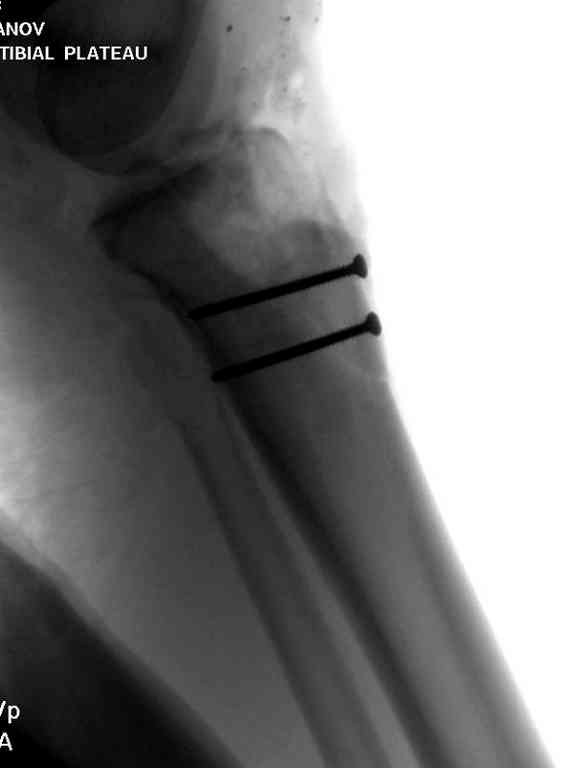

Одинокий кортикальный шуруп не удержит тибиальный бугор, сустав тибиал плато оставлен без репозиции и фиксации.

План с протезированием чересчур агрессивный, больная слишком молодая. В данный момент для удержания конструкции необходимо установить наружный фиксатор между бедром и голенью. Обработку продолжать с применением антибиотиков и вакуумирования.

Здесь применение материала Plexur http://www.plexur.com для пластики при дефектах кости у больной с огнестрельной раной латерального тибиал плато с повреждением малоберцового нерва. Несмотря на интактный медиальный мышелок, для профилактики от вальгуса установлен АВФ и сделана ангиограмма.

После нескольких обработок и вакуумирования, поэтапно сделана фиксация тибиального бугра шурупами. И окончательную фиксацию закончили латеральной пластиной для тибиал плато и установкой пластического материала.